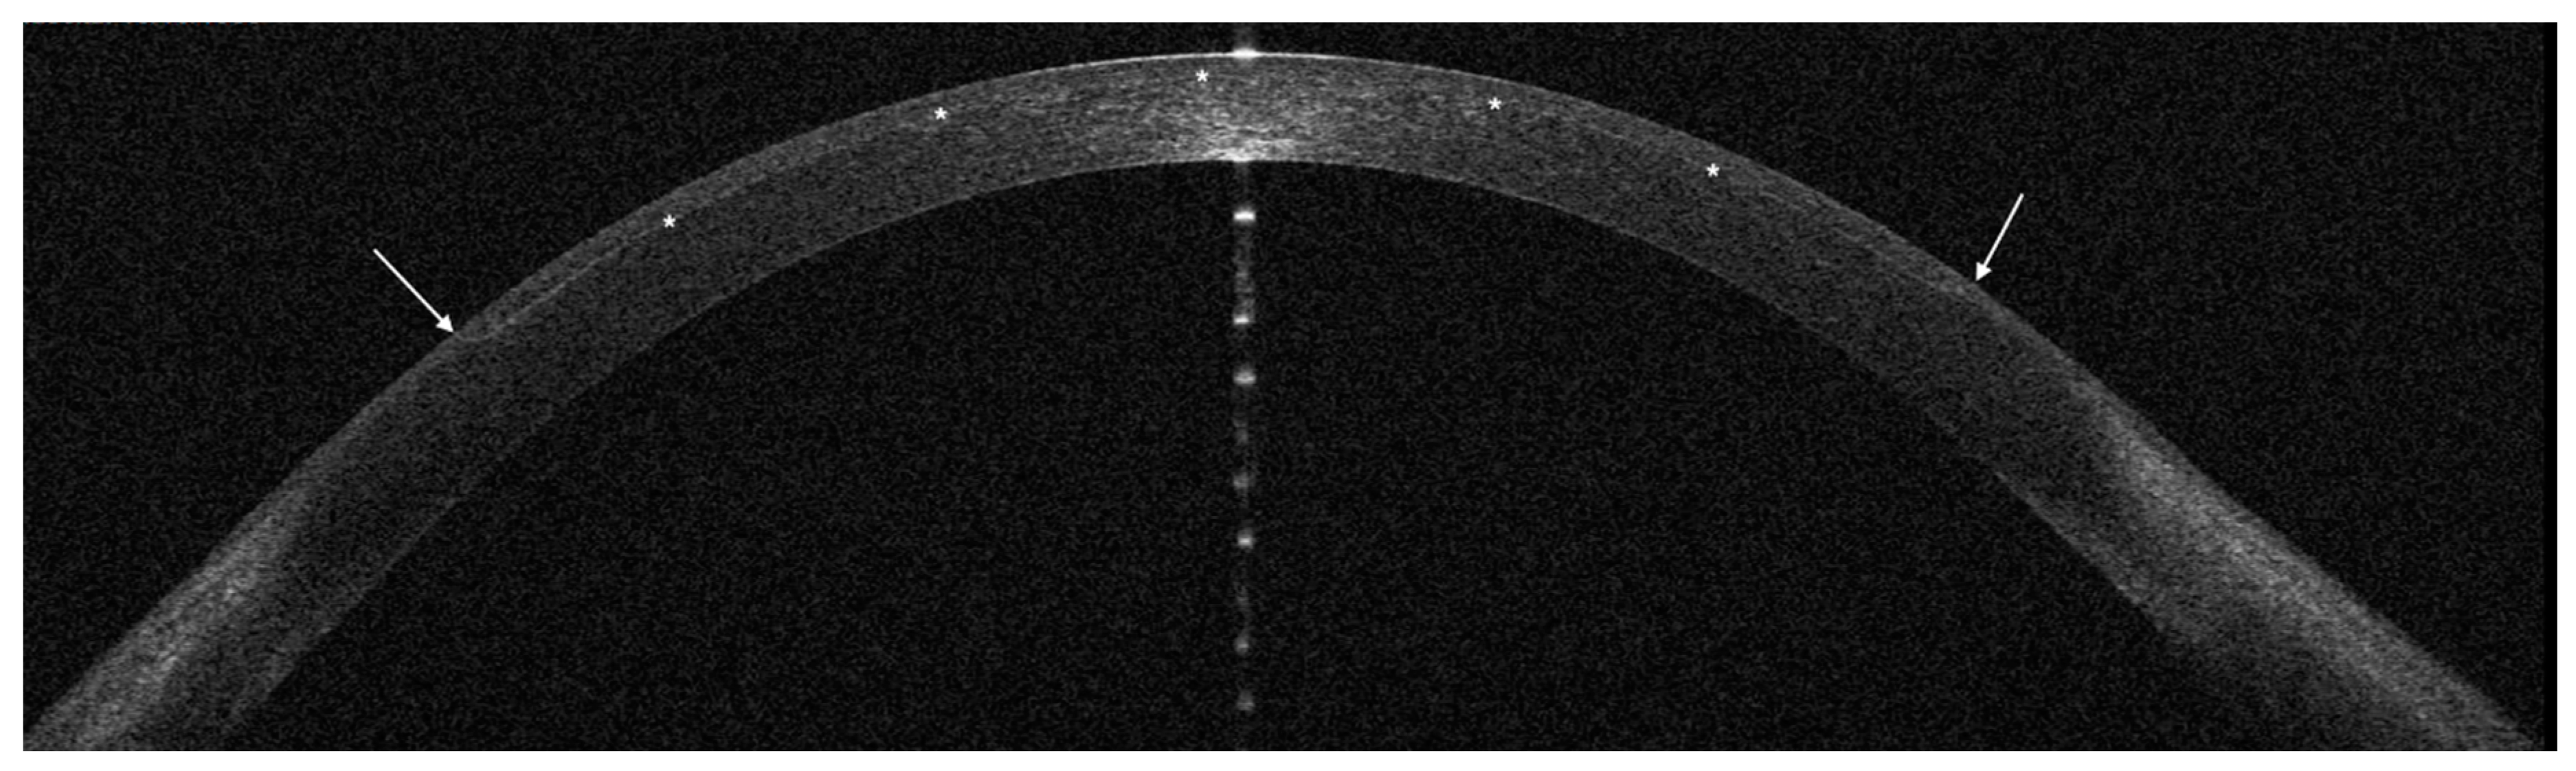

| Opaque bubble layer | 2 | 9 | 0.03^ * |